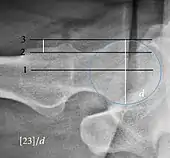

Tönnis angle Slope of the sourcil (the sclerotic weight-bearing portion of the acetabulum) 0 to 10°

• >10° is a risk factor for instability

• <0° is a risk factor for pincer impingement

Caput-sourcil angle[21] Superior to the Tönnis angle in cases without joint space narrowing or subluxation.[21] The medial point of the sourcil is at the same height as the most superior point of caput femoris. −6 to 12°[21]

• >12° is a risk factor for instability

• <-6° is a risk factor for pincer impingement